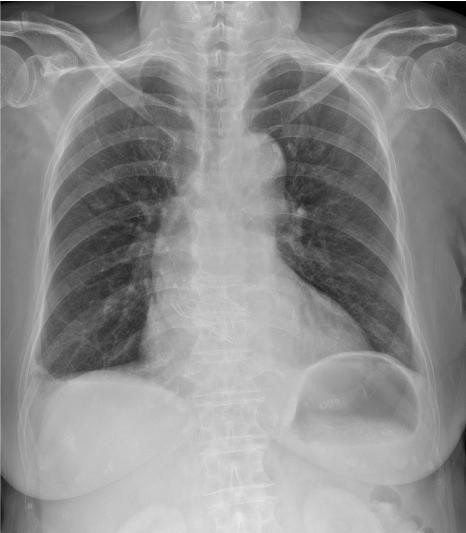

Electrocardiography revealed left bundle branch block, and chest X-ray showed small amount of bilateral pleural effusion. Echocardiography revealed moderate to severe eccentric aortic regurgitation, moderate functional mitral regurgitation, and borderline left ventricular systolic dysfunction (EF 44%).